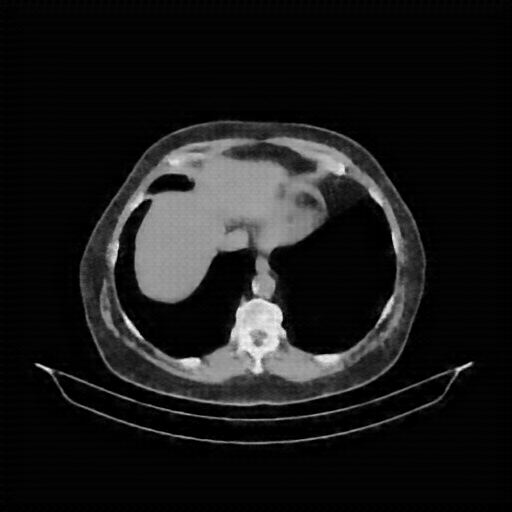

Original VENOUS CT scan

Full window (WL 1023.5, WW 4095 β†’ Low βˆ’1024, High +3071)

Actual HU range: [-160.0, 240.0]